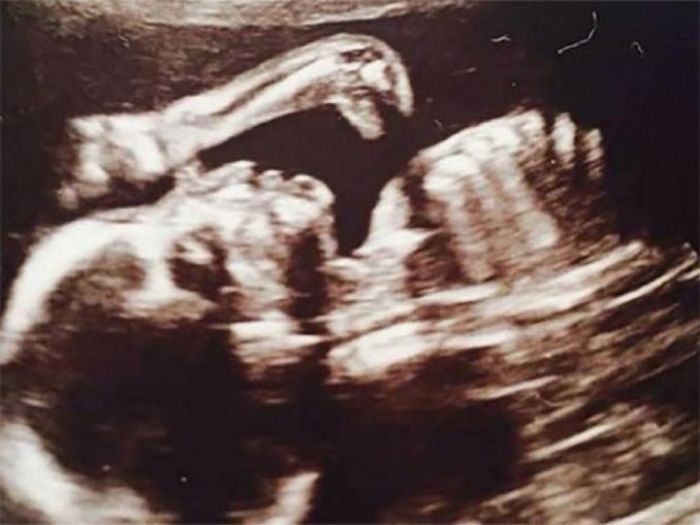

Internacionales | La curiosa situación se desató luego de realizar los estudios correspondientes para la llegada de Ruthie, la beba que espera la británica Leanne Sullivan.